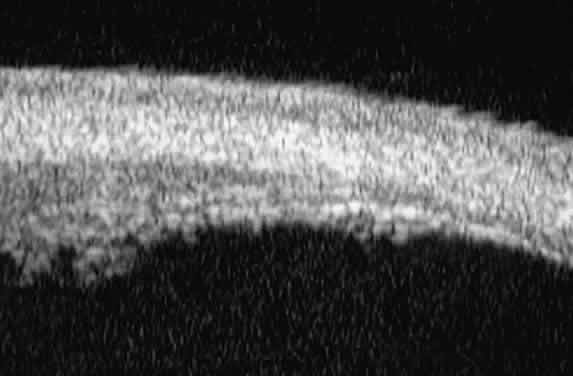

of the angle. In open-angle glaucoma, UBM can be used to measure the anterior chamber

angle in degrees, to assess the configuration of the peripheral iris, and

to evaluate the trabecular meshwork (Fig. 9).2,4 The angle configuration can be graded and compared with gonioscopic findings. In

is hazy or opaque.  Fig. 9. Angle configuration in eyes with open-angle glaucoma. A. Wide open angle with flat iris plane (D40r configuration by Spaeth gonioscopic

grading system). B. Moderately wide angle with anteriorly bowed iris plane (C30r by Spaeth

gonioscopic grading system). Fig. 9. Angle configuration in eyes with open-angle glaucoma. A. Wide open angle with flat iris plane (D40r configuration by Spaeth gonioscopic

grading system). B. Moderately wide angle with anteriorly bowed iris plane (C30r by Spaeth

gonioscopic grading system).